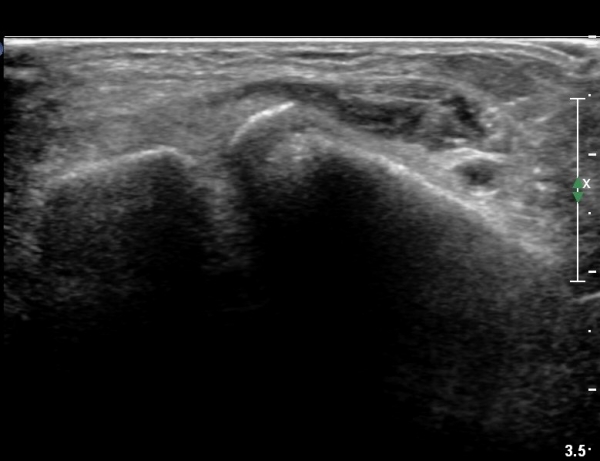

ÃÊÀ½ÆÄ °Ë»ç

CT : avulsion fracture of distal tibia at distal tibiofibulat ligament insertion.